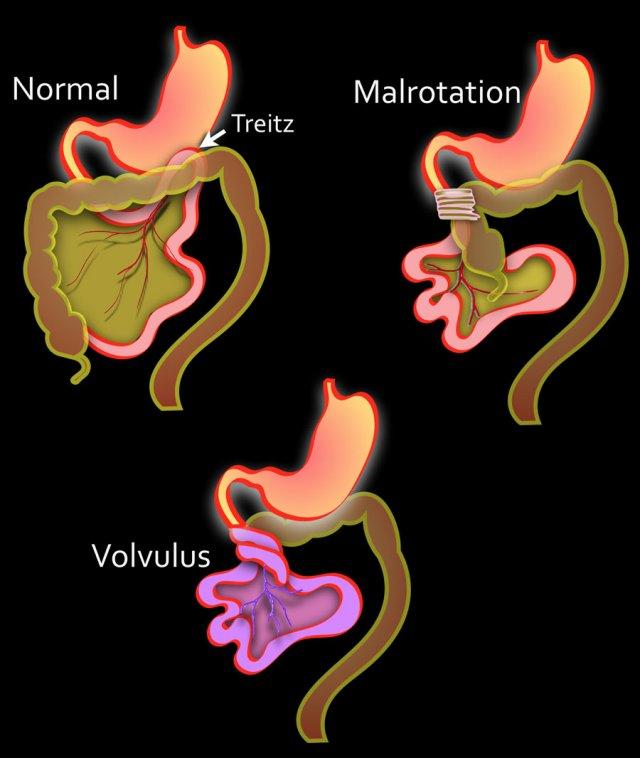

Trong quá trình phát triển phôi thai, sự tăng trưởng của ruột đòi hỏi phải thoát vị vào túi omphalomạc treo.

Vào tuần thứ mười của thai kỳ, ruột trở về khoang bụng.

Quá trình trở về này đi kèm với sự xoay ngược chiều kim đồng hồ của ruột giữa để đạt được vị trí cuối cùng với dây chằng Treitz ở góc phần tư trên trái và manh tràng ở góc phần tư dưới phải, được treo bởi mạc treo dài.

Xoay ruột bất thường xảy ra khi quá trình xoay bị gián đoạn hoặc thậm chí đảo ngược.

Hậu quả là ruột có vị trí bất thường, mạc treo ngắn và các dải phúc mạc, gọi là dải Ladd, có thể bắc qua từ manh tràng đến gan hoặc thành bụng trước.

- Trái

Tình trạng bình thường với tá tràng nằm sau phúc mạc.

Dây chằng Treitz nằm bên trái cột sống.

Ruột non chủ yếu nằm bên trái.

Manh tràng ở góc phần tư dưới phải.

Mạc treo dài.

- Giữa

Dây chằng Treitz bị dịch chuyển xuống dưới và sang phải.

Ruột non chủ yếu nằm bên phải.

Các dải xơ bắc qua đoạn thẳng đứng của tá tràng gây tắc nghẽn. - Phải

Xoắn ruột do mạc treo ngắn. Ruột thiếu máu.